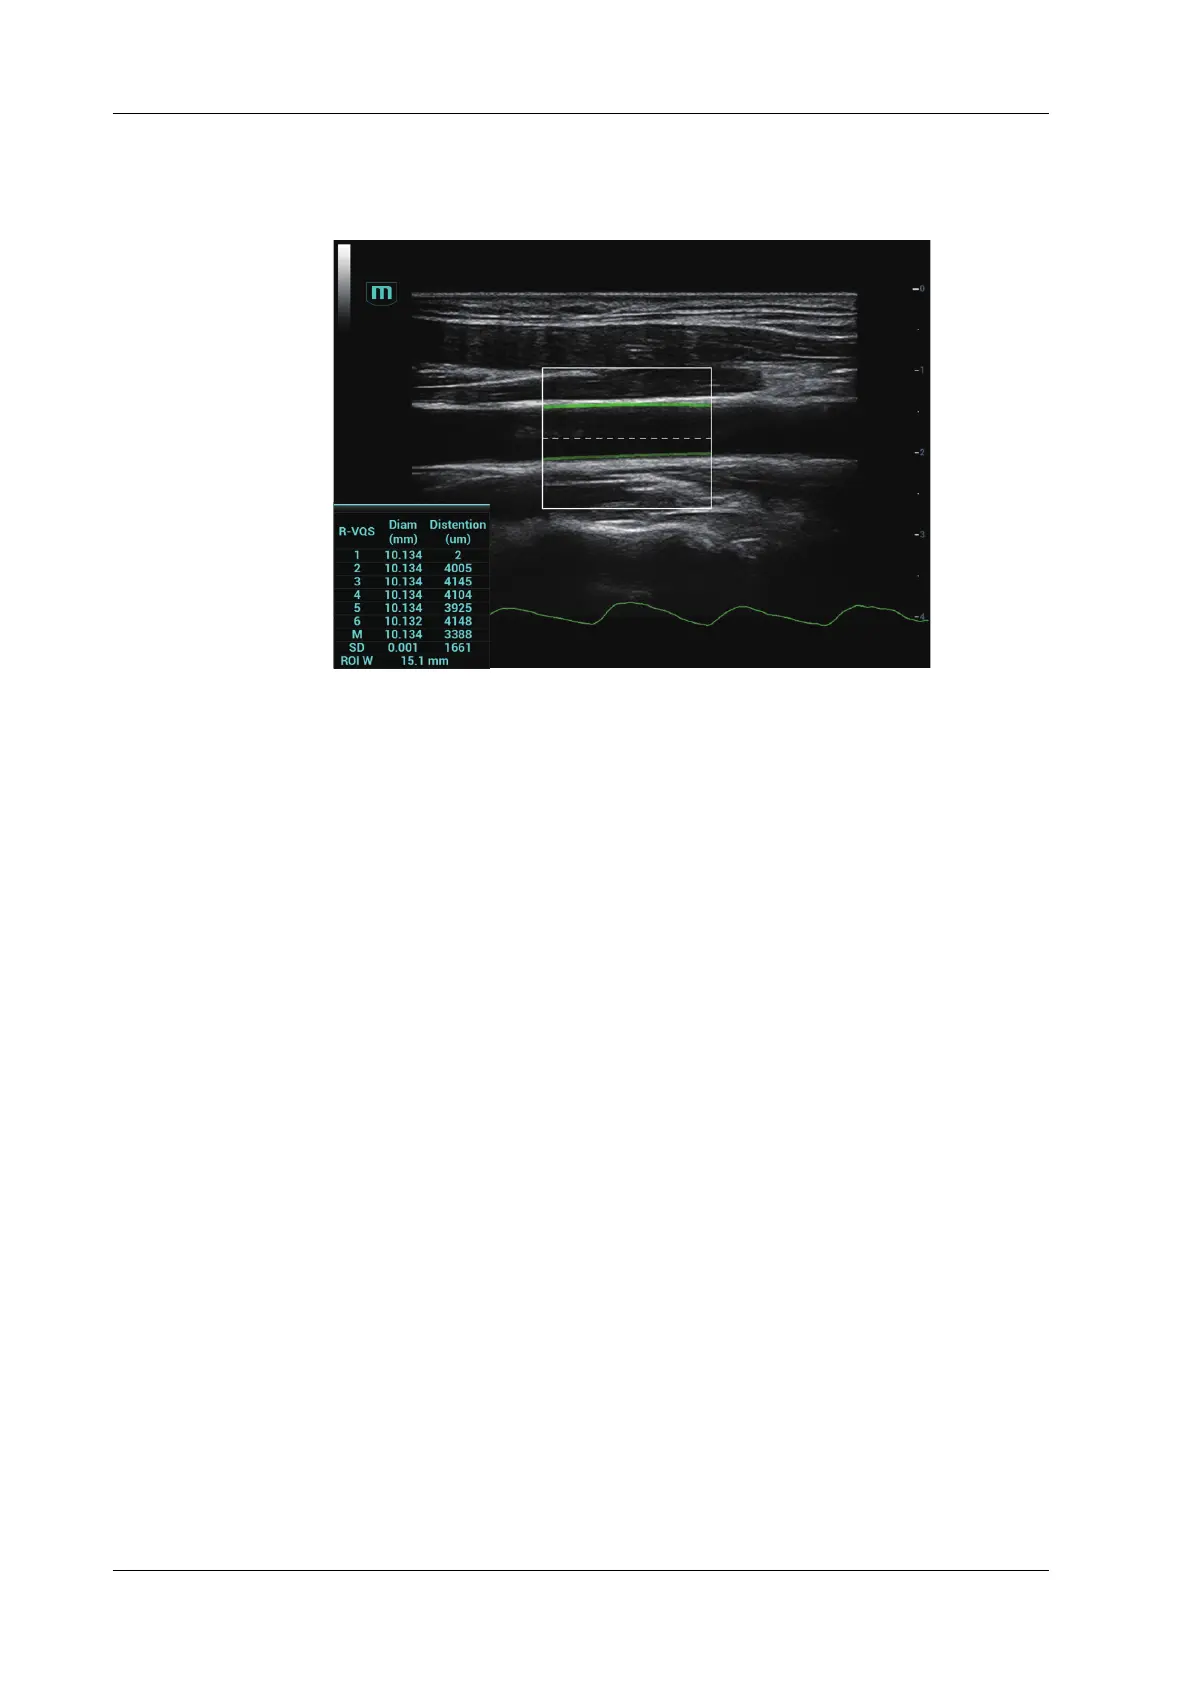

6 R-VQS (RF-data based quantification on arterial stiffness) values (6 cardiac cycles are

calculated in total), standard deviation SD and ROI length will be displayed in the result

window on the left.